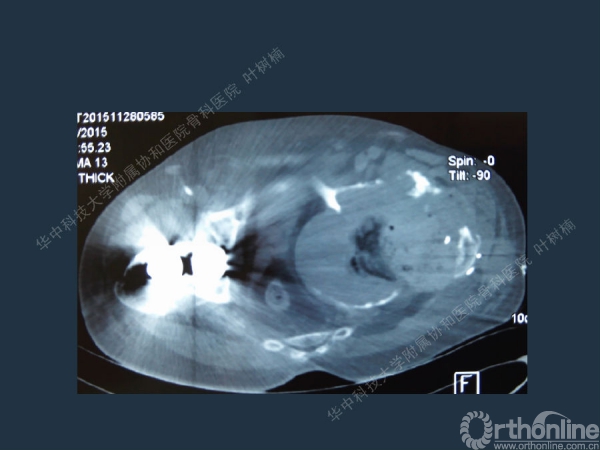

股骨侧翻修

髋臼缺损的处理